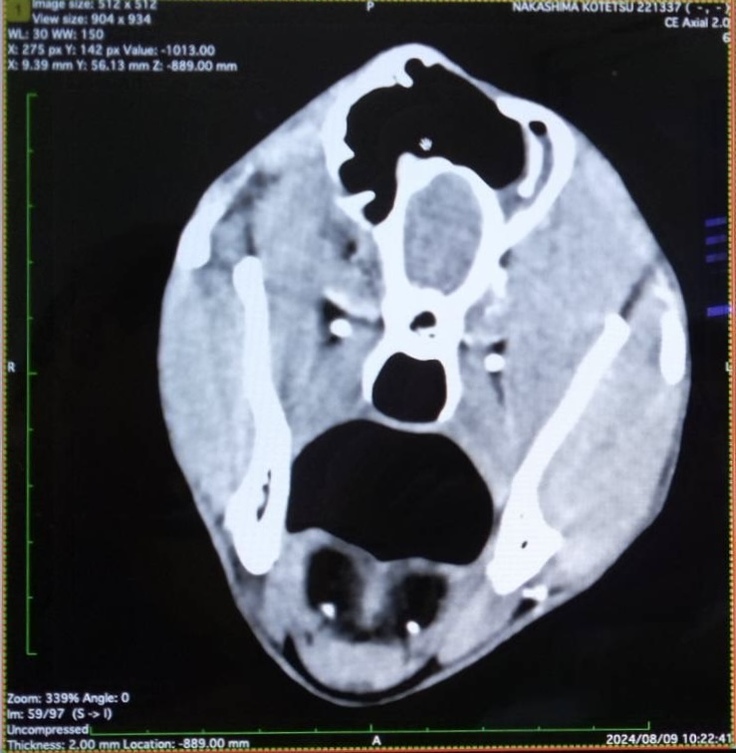

小鉄、寛解しました!!

本日、遂に画像検査を行いましたところ、腫瘍が消え、転移も無しとのことでした。

今後も抗がん剤治療は継続しなければいけませんし、進行の速い癌なので再発の可能性も非常に高いですが、お医者様からほぼ寛解と考えてもよいと思いますと言っていただけました。